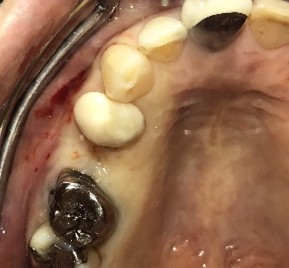

レントゲンで詳しく診てみると、虫歯が歯根のほうまで進行し、保存することができないことがわかり、抜歯しました。抜歯後、骨が大きく欠損していましたので、骨造成を行いインプラントを2本埋入しました。

Before

【抜歯後】